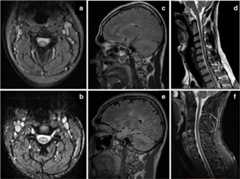

Fig. 1.

(a) and(b): axial T2-weighted cervical spine MRI of the index case 1, treated with ETN for 8 months for PsA, who was diagnosed with MS on follow-up.(a) At initial presentation, a central posterior demyelinating lesion on C3 level that showed gadolinium enhancement on T1-sequences (not shown).(b) Four years after etanecept discontinuation, disappearance of the lesion.(c)–(f) Brain and cervical spine MRI of the index case 2, with AS and a family history of MS, treated with adalimumab for 36 months, who was also diagnosed with MS.(c) Brain flair and(d) cervical spine T2-weighted sagittal MRI at symptom onset, and(e)–(f) 4 years after anti-TNF-a cessation. Note the increase of cerebral demyelinating lesions, with marked atrophy, and the disappearance of the lesion on C7 level